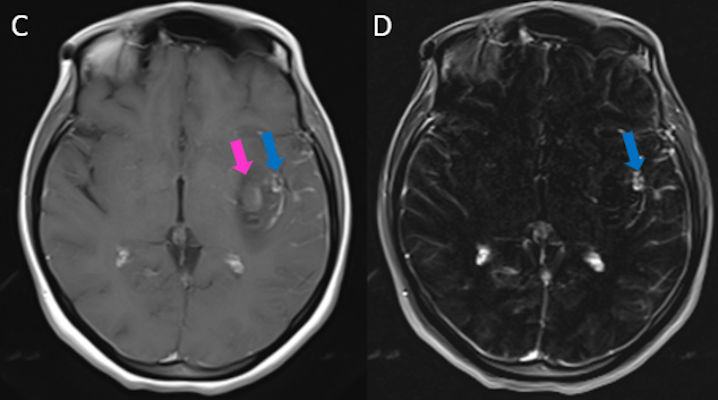

- DSA görüntülemede (G) sol MCA M2 segmentinde anevrizmatik dolum fazlalığı izleniyor (ok). Bu anevrizmaya eş zamanlı koil işlemi yapılıyor (oklar) ve işlem sonrası kontrol BT anjiografi görüntüsünde (H) metalik koil materyali izleniyor (ok).